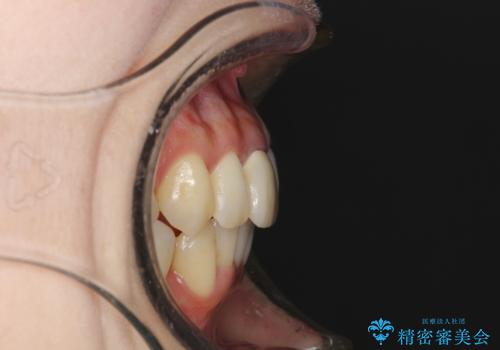

- 上下のがたつきを主訴に来院された患者様です。

上下の前歯と奥歯にがたつきがありました。

上下の奥歯を後方に移動させるのと、歯と歯の間をわずかに削ることでスペースを作り、歯を並べる計画としました。